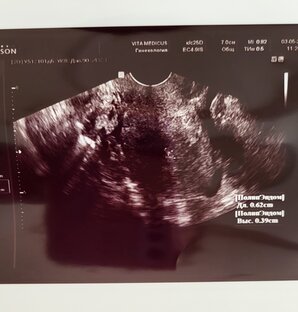

Эндометриоз. Моя история

Всем привет. Давно на моей странице нет ни видео ни постов. Не просто так. Я себя не очень хорошо чувствую. Сейчас расскажу что происходит от самого начала и до сего дня. Так что приготовьтесь будет долго. Пишу о наболевшем ... Моя история начинается в 2016 году. Прошло 1,5 года с момента вторых родов. Лето... мы ездим на дачу и так совпадает что как на дачу так критические дни, и в животе колики. Сначала списывала эти колики на плохую воду на даче. Но потом дача закончилась, а колики остались, да как остались?! Пуще прежнего болеть начало все...